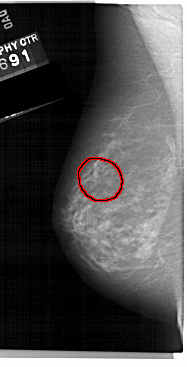

A_1224_1.LEFT_CC

FILE: A_1224_1.LEFT_CC.OVERLAY

TOTAL_ABNORMALITIES 1

ABNORMALITY 1

LESION_TYPE MASS SHAPE IRREGULAR MARGINS SPICULATED

ASSESSMENT 4

SUBTLETY 3

PATHOLOGY MALIGNANT

TOTAL_OUTLINES 1

BOUNDARY